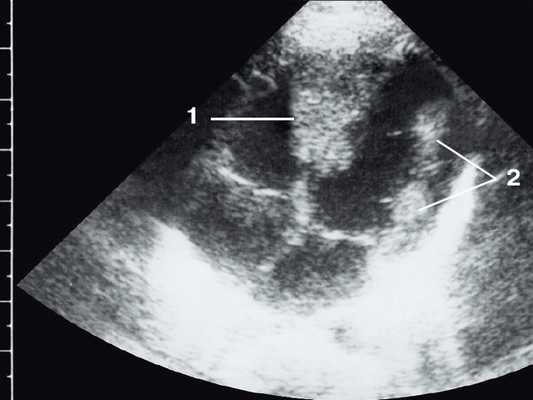

Широкое внедрение в практику ультразвуковой диагностики позволило перейти от аутопсийной статистики к прижизненному выявлению. Эхокардиография - первый метод выявления рабдомиомы сердца и контроля состояния пациента в динамике. Учитывая очень большое число семейных случаев, необходимо обследование всех ближайших родственников, особенно при наличии у них пятен цвета кофе с молоком, депигментированных по типу шагреневой кожи, параунгвальных и параореолярных фибром, ранних миом матки, инфантильных спазмов, судорожных припадков и других признаков факоматозов. При семейных обследованиях рабдомиомы сердца могут выявляться у совершенно бессимптомных носителей (рис. 1, 2).

Рис. 1. Эхокардиограмма ребенка (девочки) с рабдомиомой. Крупный узел рабдомиомы в межжелудочковой перегородке (1) и менее крупные узлы в задней стенке левого желудочка (2). Эхоплотность образований выше, чем миокарда.

Рис. 2. Эхокардиограмма матери этого же ребенка. В межжелудочковой перегородке несколько эхоплотных образований (стрелки).